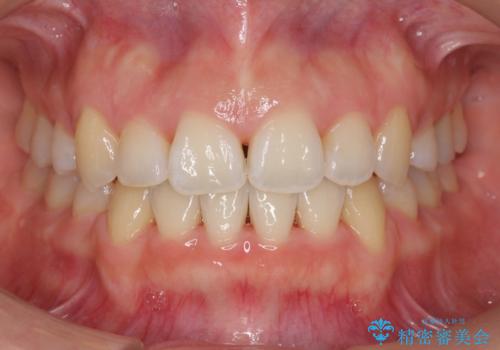

ワイヤー矯正は時間はかかりますが、仕上がった後の自然な美しさは他の追随を許しません。

歯を抜いたことで、口元が下がって、横顔も理想的なラインになりました。

- 前歯のがたつきと正中のずれを主訴に来院。

小臼歯を4本抜歯しています。